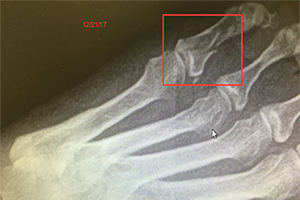

A female patient presented with a broken toe resulting from a slip on the ice December 20th, 2017. This finding was confirmed with x-ray the following morning. She started a regimen with the Wei Fastt patches. Additionally, she started on 1 capsule, 3 times daily of the Wei product Martial. This product helps to activate blood circulation in the bones to expedite the healing process of the Fastt patch. Furthermore she also added in a vitamin product, Intenzyme Forte from Biotics Research Corporation, to help reduce swelling and inflammation. Along with these therapies she increased her calorie and total protein intake to address a nutritional need in her body for further speed in healing.